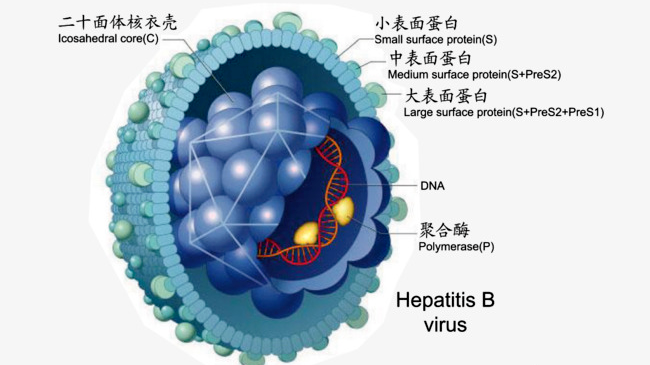

2、DNA的特殊結構

當病毒來到肝細胞膜時,找到可入侵的受體,然后外殼蛋白HBsAg(病毒表面抗原) 去掉。進入肝細胞,直接進入細胞核;病毒到達目標后,取下內衣殼,病毒DNA帶著自己的DNA聚合酶像助手一起進入肝細胞核。此時,乙肝病毒DNA,就會在DNA在聚合酶的作用下,有兩種可能性:

①補齊一條鏈,形成兩個閉環的共價DNA,稱cccDNA,乙肝病毒的主要生存方式是結構非常穩定;

②制造病毒外殼(HBsAg)的那一段DNA,直接插隊到我們的肝細胞DNA中間,整合在一起。病毒就這樣,躲在肝細胞核里,不斷讓肝細胞幫它復制后代。